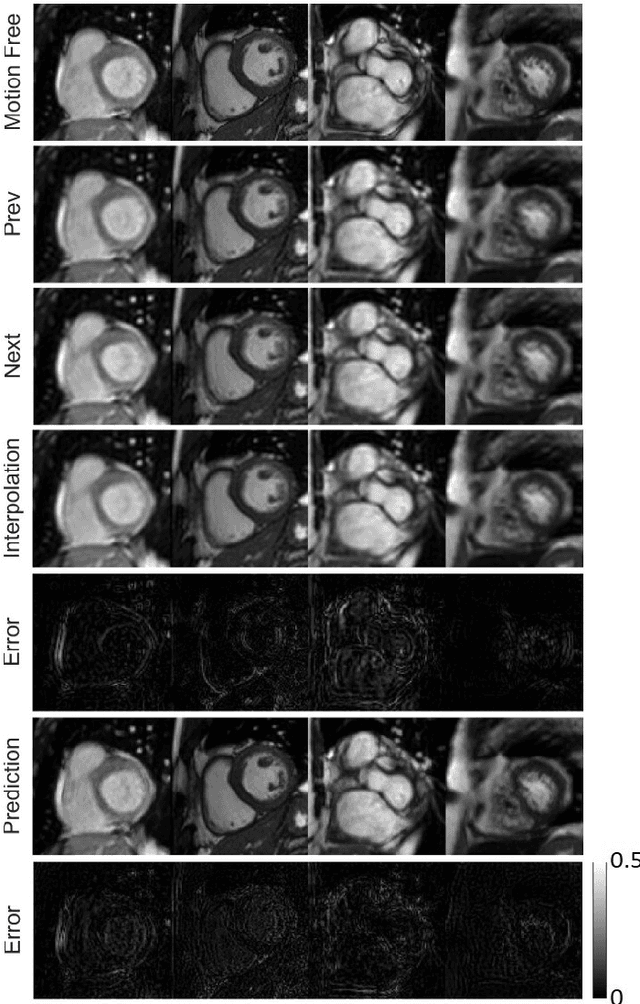

Abstract:Cine cardiac magnetic resonance imaging (MRI) is widely used for diagnosis of cardiac diseases thanks to its ability to present cardiovascular features in excellent contrast. As compared to computed tomography (CT), MRI, however, requires a long scan time, which inevitably induces motion artifacts and causes patients' discomfort. Thus, there has been a strong clinical motivation to develop techniques to reduce both the scan time and motion artifacts. Given its successful applications in other medical imaging tasks such as MRI super-resolution and CT metal artifact reduction, deep learning is a promising approach for cardiac MRI motion artifact reduction. In this paper, we propose a recurrent neural network to simultaneously extract both spatial and temporal features from under-sampled, motion-blurred cine cardiac images for improved image quality. The experimental results demonstrate substantially improved image quality on two clinical test datasets. Also, our method enables data-driven frame interpolation at an enhanced temporal resolution. Compared with existing methods, our deep learning approach gives a superior performance in terms of structural similarity (SSIM) and peak signal-to-noise ratio (PSNR).